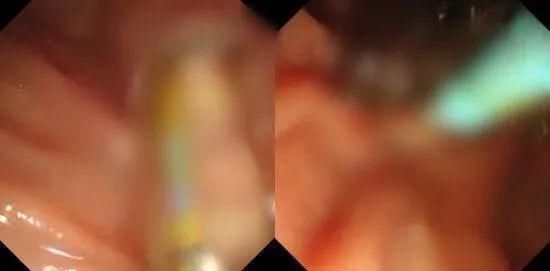

为了进一步了解患者胆总管的情况,团队决定为阿婆进行ERCP(经内镜逆行性胰胆管造影术),并在内镜下行胆总管支架植入手术,打通梗阻的胆总管。团队将治疗方案与家属进行沟通,得到了家属的理解和支持。2020年12月29日,消化内科谈朋生医生和内镜中心护士肖强一起,为陆阿婆进行了ERCP,这一查可就让“真相大白”——原来,陆阿婆的症状并不是之前高度怀疑的胆总管肿瘤引发的,而是堵住了胆总管的大量结石!两人历时1.5个小时,把陆阿婆胆总管内的石头全部取了出来。

查到明确病因并及时解决,还“改判”了原本肿瘤的定论,执着的消化内科团队和神奇的ERCP立下大功,阿婆和家人都开心不已。术后,阿婆的胆红素即恢复正常,肝酶大幅度下降。术后第三天,阿婆精神也好了,拉着谈医生的手连连感谢,并且已经可以进食,无发热、胰腺炎并发症,再过1-2天即可出院啦!

据介绍,ERCP手术创伤小,并发症较外科手术少,是当今胰胆疾病重要的治疗手段,深受患者欢迎。亭林医院消化内科团队敢于挑战、严格基于事实,实实在在为患者找病因、除病痛的态度,更值得点赞!资料:i亭医